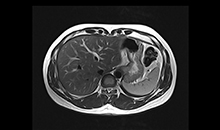

Uygulama Görüntüleri